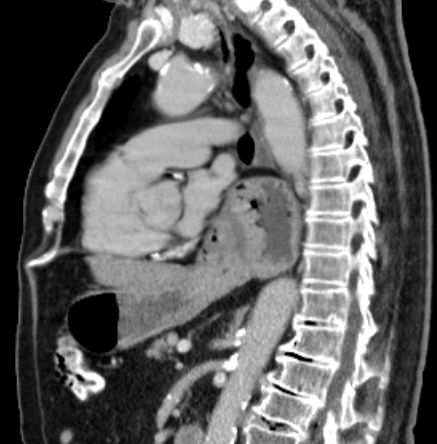

Hiatus - Hernie 83-jähriger Patient, der seit 2 Wochen Schluckbeschwerden mit unmittelbarem Erbrechen nach Nahrungsaufnahme hat. Das CT zeigt eine breite Zwerchfellhernie mit Teilen des Magens.

Die hintere Wand des intrathorakalen Magens ist verdickt: Adenokarzinom.

Der Ösophagus ist dilatiert und distal wandverdickt.